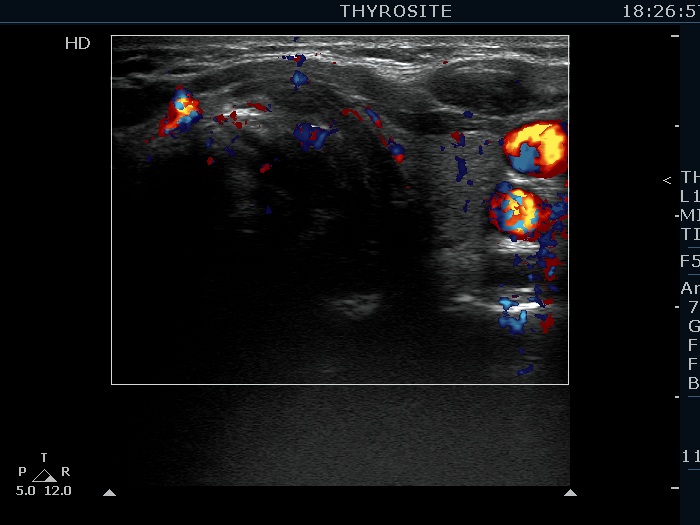

Extrathyroidal spread - case 2113 (ultrasonographic picture 12)

Left lobe, transverse scan, color Doppler mode. The vascularization is not specific.